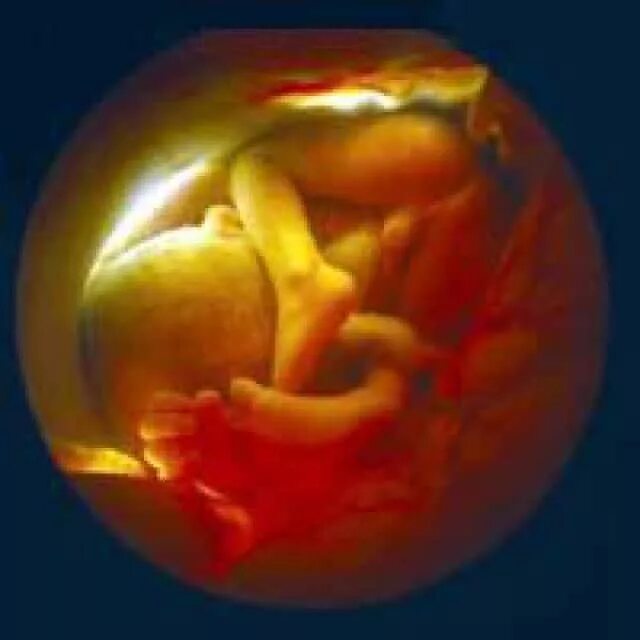

31 неделя беременности тянет